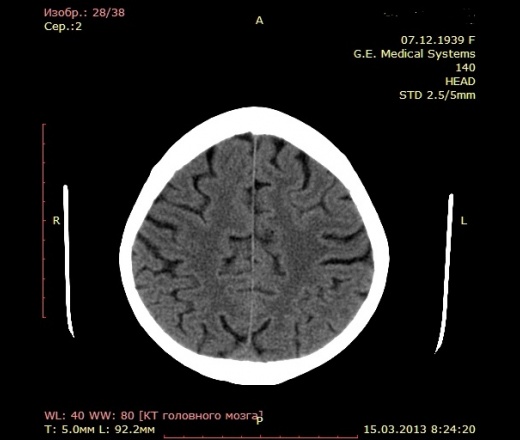

А как по мне, то тут геморрагический инсульт. Есть дислокация срединных структур слева.

Геморрагический инфаркт левой височной доли (в проекции таламуса слева) как правильно по локализации сам не знаю, скорее все таки таламус, со смещением срединных структур вправо, третий и левый боковой желудочек частично компримированы, формируется зона перифокального отека

Описывайте как геморрагический инсульт с объемным действием (смещением) на срединные структуры мозга. Померяйте плотности для оценки стадии. А различить на КТ две обговариваемые формы думаю нельзя. Разве что при пропитывании не будет такой четкой динамики изменения плотности очага. В литературе не встречал.